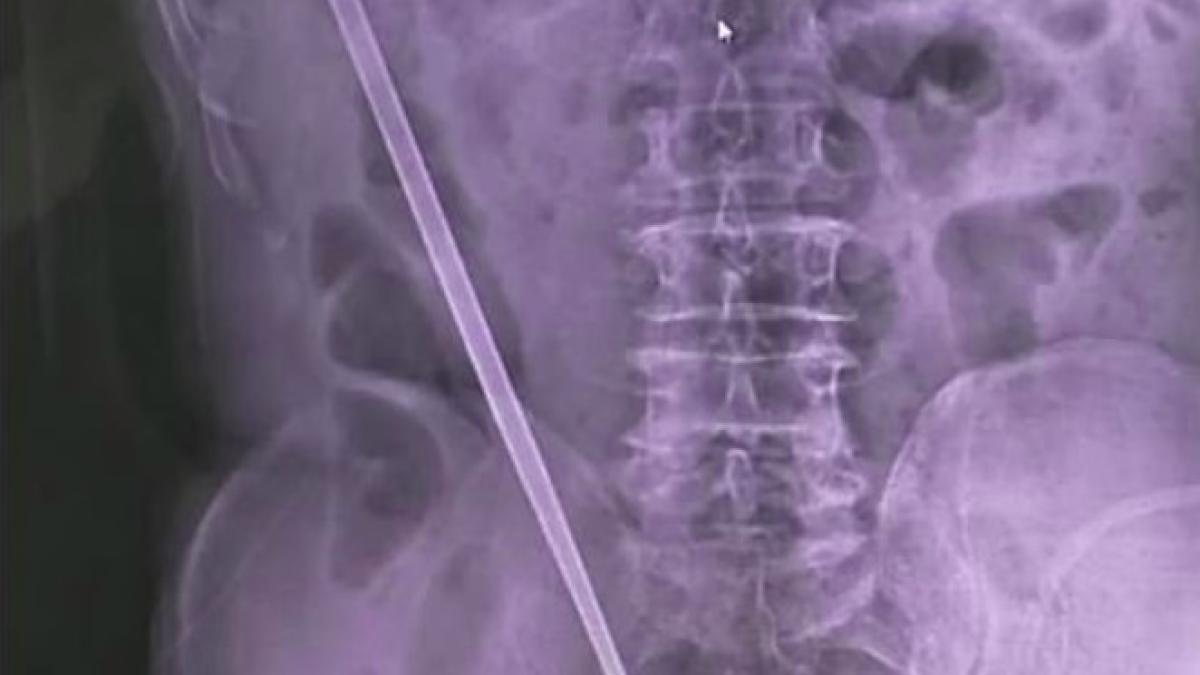

A ajuns la spital cu un băț de 25 cm în ABDOMEN. Explicația HILARĂ a accidentării

Un bărbat de 68 de ani a ajuns la doctor cu un bețigaș în stomac, după ce și l-a înfipt în posterior „din curiozitate”.

Un bărbat de 68 de ani a ajuns la doctor cu un bețigaș în stomac, după ce și l-a înfipt în posterior „din curiozitate”, conform Daily Mail.

Vârstnicul, rezident al Chinei, a declarat că a vrut să-și controleze acea parte a corpului, după ce a făcut hemoroizi. Doctorii au făcut descoperirea șocantă atunci când bărbatul s-a prezentat la spital cu dureri abdominale severe.

Pacientul a fost externat din spital după ce medicii i-au scos bețigașul de metal din intestine. Relatările presei locale nu au precizat lungimea bețigașului, dar, de obicei, chinezii utilizează bețigașe de 25 de centimetri.

Bărbatul în vârstă a vizitat spitalul din Xiangyang, Hubei, pe 22 aprilie, cu dureri abdominale severe, a transmis un doctor, sub anonimat.

„Un medic de gardă i-a făcut o radiografie și a observat obiectul de metal în cavitatea abdominală a bărbatului”, a spus acesta. „În timpul operației, am reușit să eliminăm bețigașul de metal din colonul său”.

Bătrânul le-a mărturisit medicilor că a vrut să folosească bețigașul pentru a-și investiga hemoroizii „din curiozitate”.